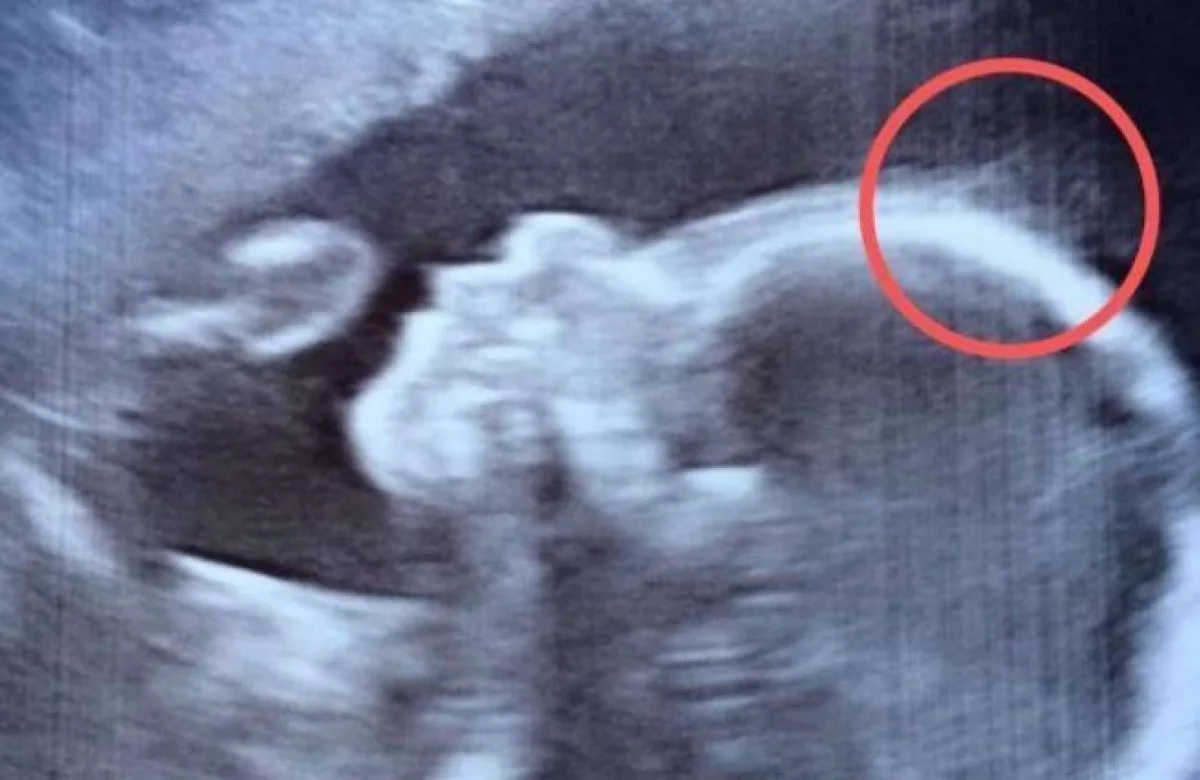

Con el paso de los meses, acudieron a una revisión médica de rutina a causa del embarazo y en el ultrasonido que le practicaron, la futura madre notó lo que parecían ser muchas líneas alrededor de la cabeza de su bebé.

Se trataba de la gran cabellera que la niña tenía y que bien le haría acreedora al premio de 'La más frondosa cabellera' de un recién nacido.

La nena llegó a este mundo con una gran cabellera, tanto, que era visible desde el ultrasonido del bebé.